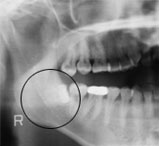

埋伏智慧齒拔除